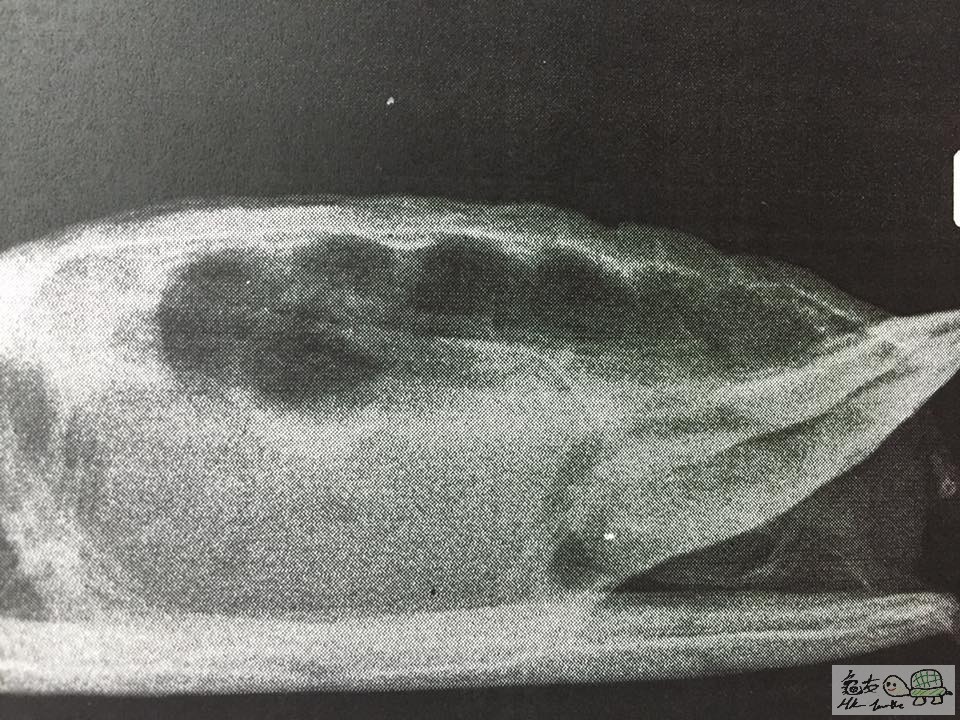

月頭帶佢睇過第二個醫生,先去照左X光同抽血,做手術除切突出部份(唔洗好似上次咁要駁針~)

可以睇到有小小肺炎徵狀,需要每3日打一次抗生素

除左肺炎,醫生指佢開始有卵泡,日後如果無法排出就會有卵塞的情況,到時就要絕育!